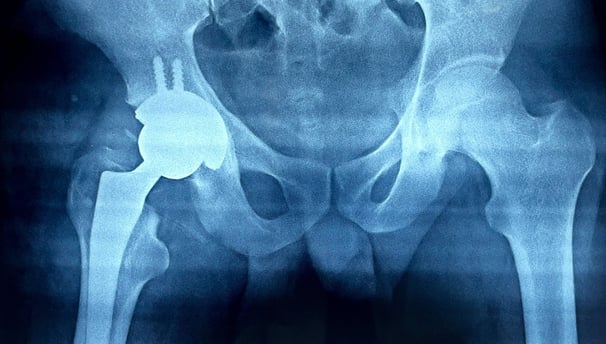

Joint Replacement

Advanced techniques for joint replacement surgery to restore movement and relieve pain effectively.